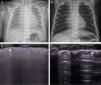

La ecografía pulmonar objetivó un patrón compatible con SDR en todos los casos (fig. 1C): líneas B compactas, difusas y simétricamente distribuidas en ambos pulmones con una línea pleural engrosada e irregular. En todos los casos se verificó la posición transtraqueal del TET. El «deslizamiento pulmonar» derecho y la excursión diafragmática derecha fueron visibles en todos los casos durante la ventilación pero en 2 casos no se objetivó ni «deslizamiento pulmonar» izquierdo ni excursión diafragmática izquierda, objetivándose en ambos el signo del «pulso pulmonar». Uno de los 2 casos fue sospechado previamente mediante auscultación pulmonar.

A) Radiografía de tórax en un neonato con síndrome de distrés respiratorio. B) Radiografía de tórax del neonato en el momento del alta. C)Ecografía pulmonar longitudinal del mismo paciente, evidenciándose un patrón difuso y compacto de líneas La flecha indica la pleura engrosada e irregular. Una vez el paciente se encuentra intubado, es posible visualizar el «deslizamiento pulmonar» en ambos pulmones. D) Ecografía pulmonar longitudinal del paciente con una línea pleural normal ecogénica. Las líneas A son finas y paralelas unas a otras, pudiéndose observar en el pulmón el reflejo de sombra costal confirmando el patrón normal sin líneas B o líneas de cometa.

La ecografía pulmonar realizada antes del alta, reveló un patrón pulmonar normal (fig. 1D).